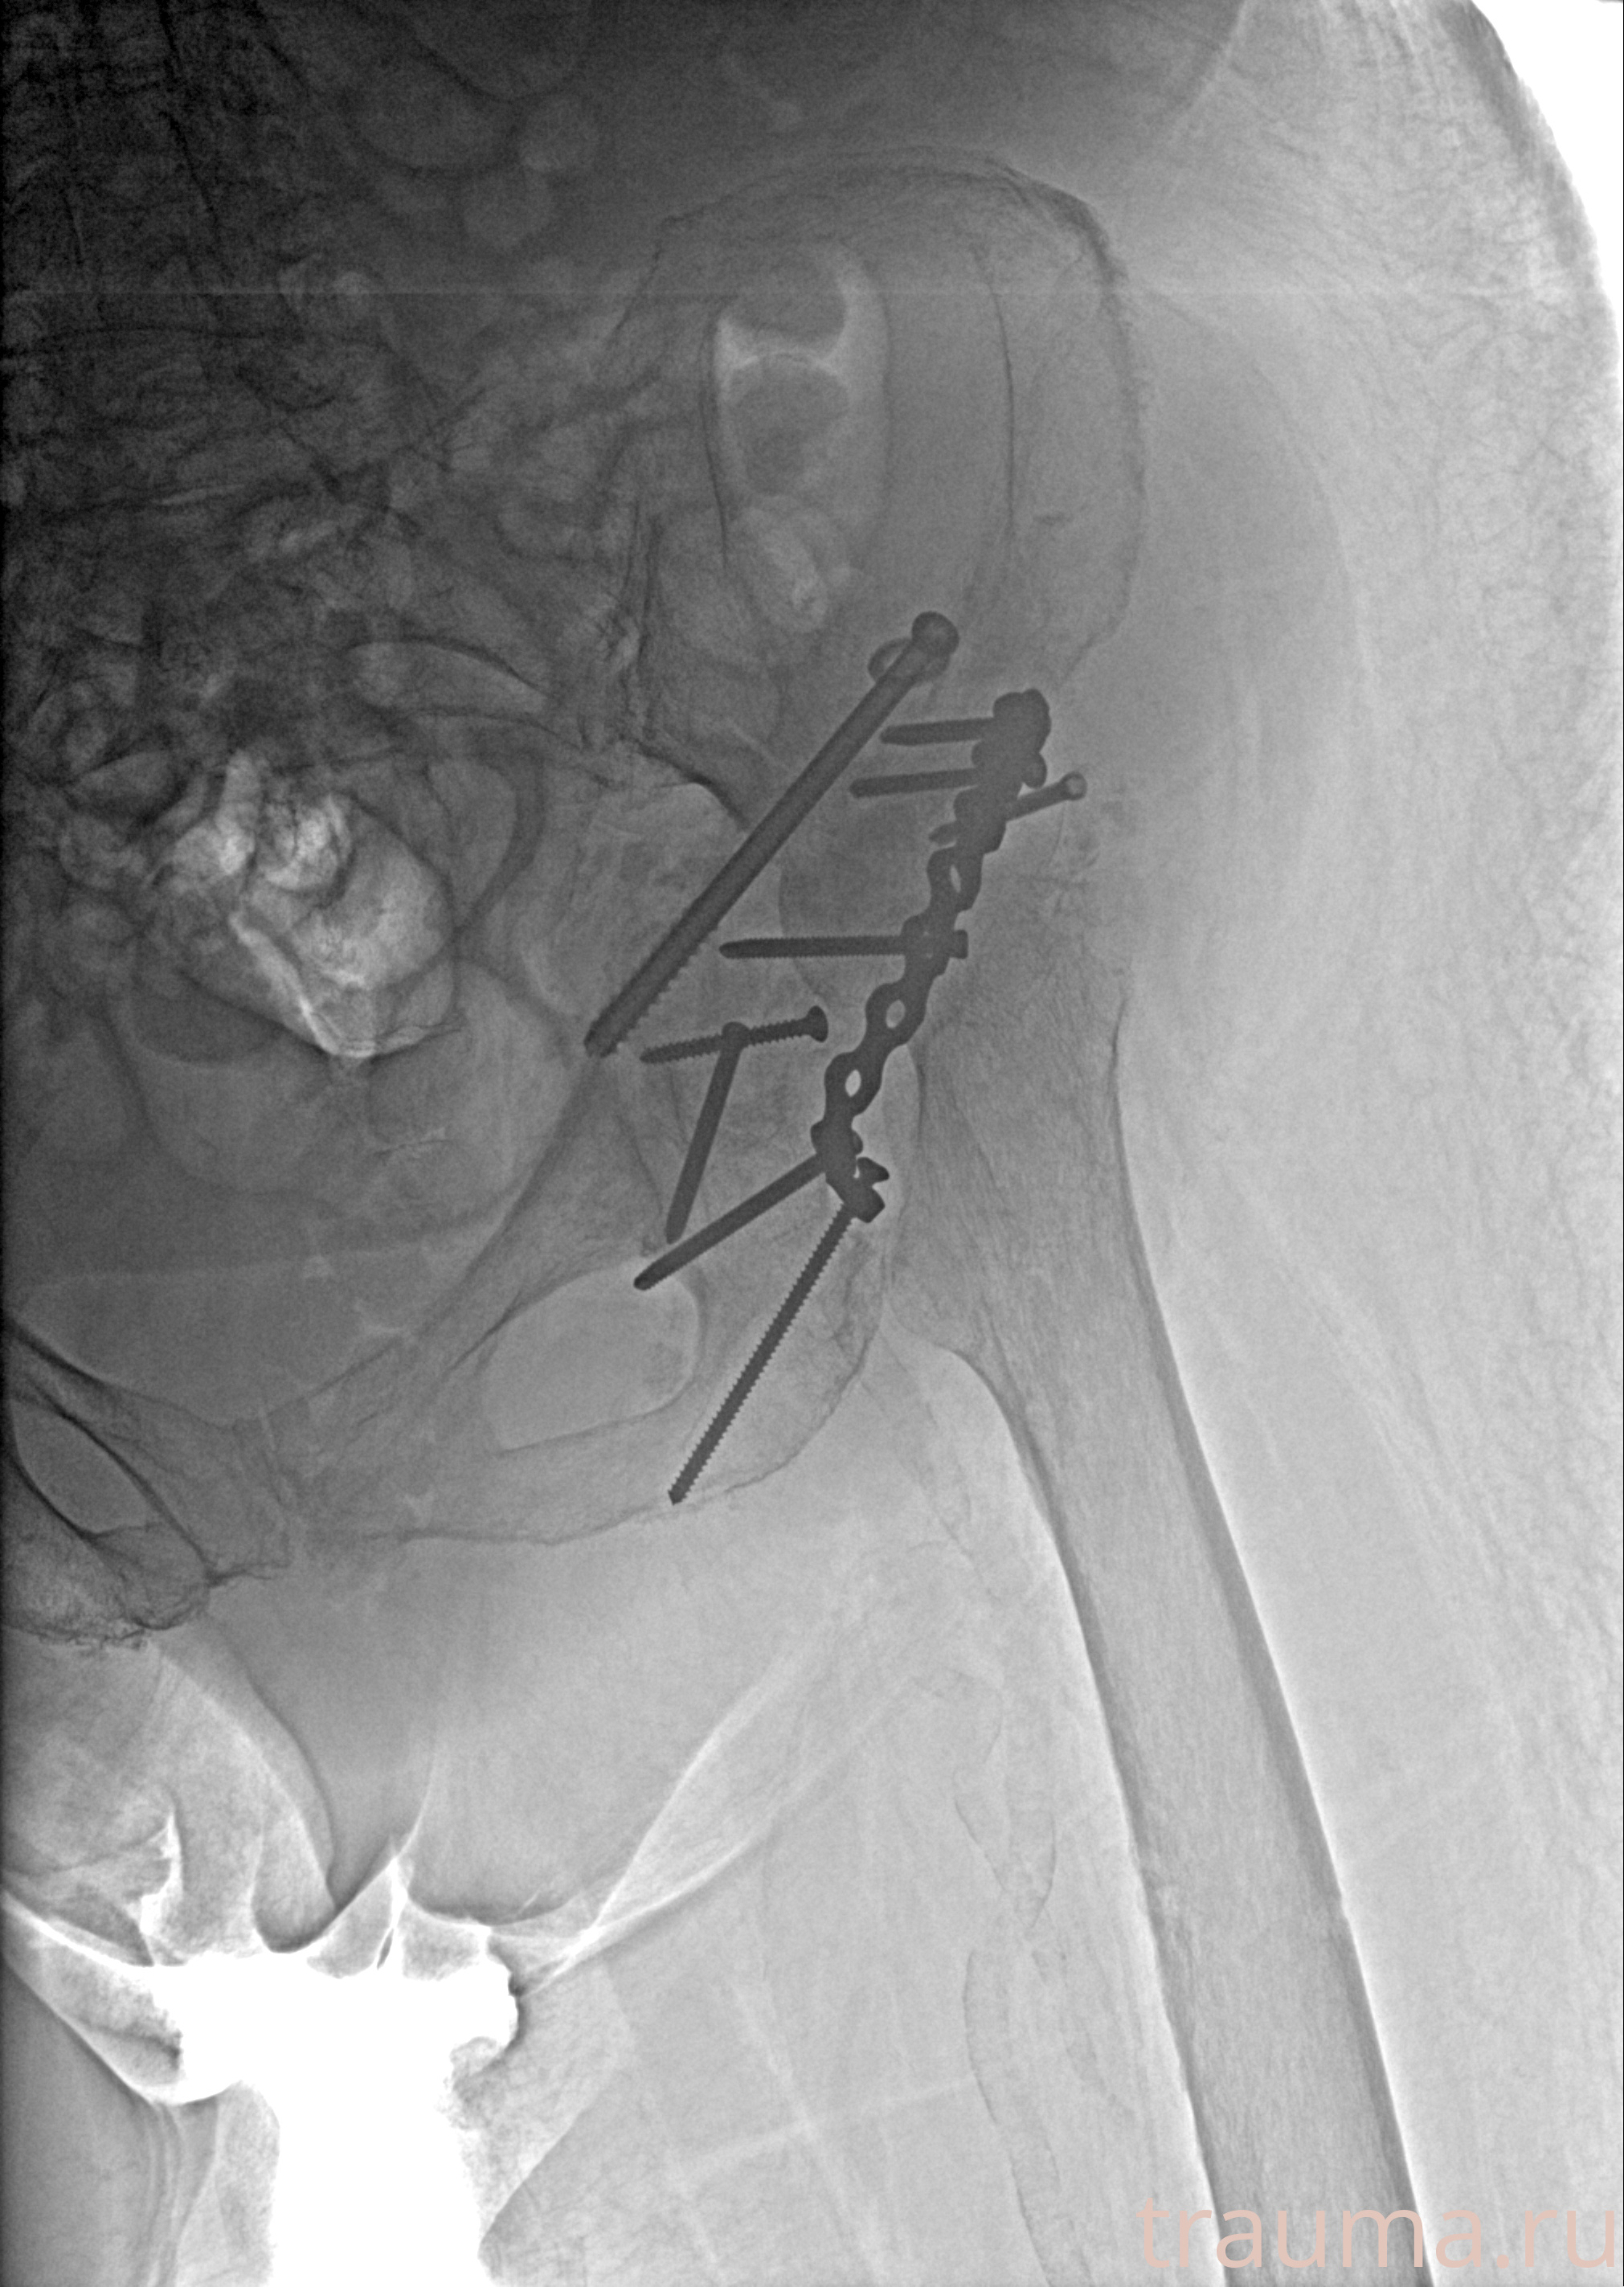

Рентгенограммы